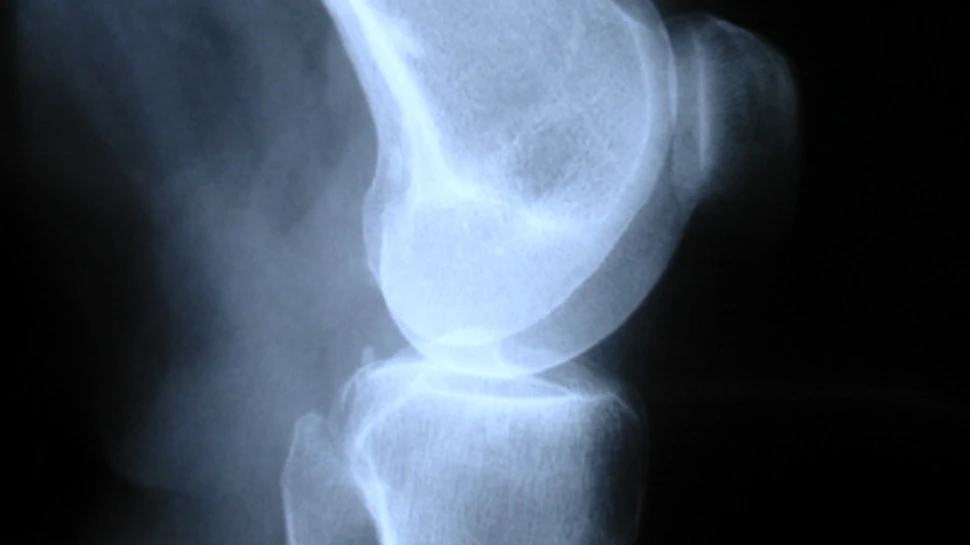

Cercetatorul Cameron Lutton, membru al universitatii australiene, sustine ca biomaterialul activeaza stadiile initiale ale vindecarii osoase. Atunci cand un os se fractureaza, are loc un raspuns foarte rapid de inflamare locala, in cadrul caruia cheaguri de sange si celule specifice sunt atrase in zona de avarie. Aceste celule produc o cascada de proteine si hormoni care stimuleaza formarea unei noi structuri osoase. Totusi, atunci cand ruptura este prea violenta, acest proces natural devine insuficient pentru ameliorarea problemei.

Biomaterialul creat de oamenii de stiinta ai Universitatii Tehnologice din Queensland, in parteneriat cu cei ai Stryker Australia, incurajeaza procesul natural de vindecare al corpului, sustinand cresterea osoasa. Cheia functionarii acestui material biologic este structura sa de suprafata, realizata dintr-un aranjament special de polimeri care atrag proteinele potrivite in zona osului ranit. “Stim ca materialul face ceea ce trebuie cu sangele pentru a incepe regenerarea osoasa”, sustine Lutton, “iar urmatorul pas este sa determinam daca si restul etapelor din procesul vindecarii are loc.” Daca biomaterialul va trece cu success de ultimele testari, se va incepe utilizarea sa la scara larga, pentru tratarea pacientilor cu serioase defecte si rani osoase.